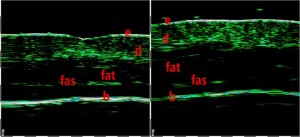

-Υπέρηχος Υψηλής Συχνότητας (HFUS) και Ιστολογία